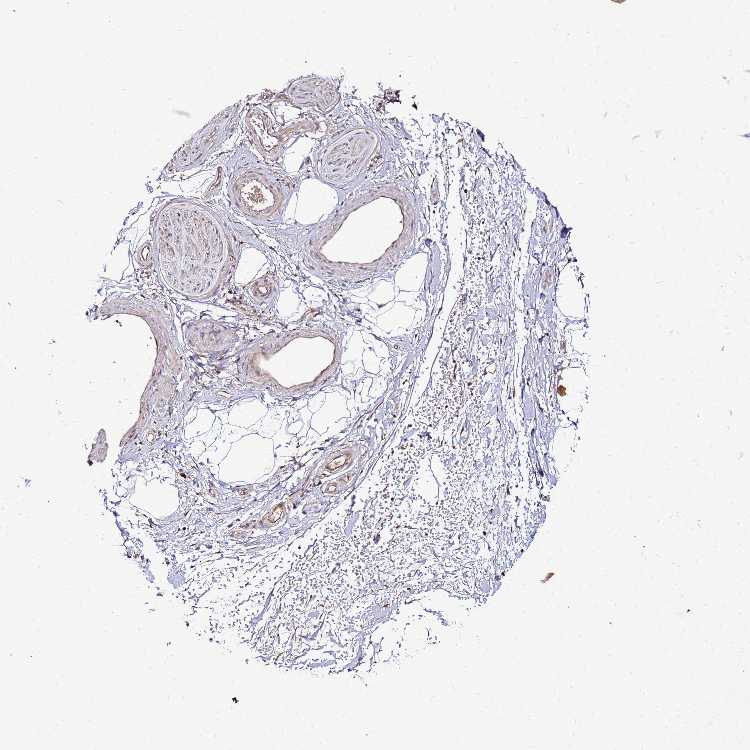

SOFT TISSUE 1 - Antibody stainingi

Antibody staining in the annotated cell types in the current human tissue is reported as not detected, low, medium, or high, based on conventional immunohistochemistry profiling in selected tissues. This score is based on the combination of the staining intensity and fraction of stained cells.

Each image is clickable and will lead to virtual microscopy that enables deeper exploration of all samples and also displays staining intensity scores, fraction scores and subcellular localization as well as patient and tissue information for each sample.

Antibody HPA023038

Fibroblasts Medium

Peripheral nerve Medium